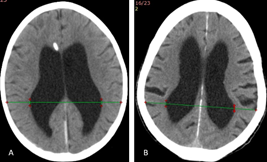

The severity of hydrocephalus can be established with the standardized method used by Choudhury in 1995,15 determining the ventricular/biparietal (V/BP) ratio (mathematical ratio) from a computed tomography of the skull (axial slice). The V/BP ratio is calculated from the measurements of the ventricular diameter (parietal part of the body of the ventricles, drawing a line between the lateral walls of both lateral ventricles) and the biparietal diameter (on the same "ventricular line" is extended to the internal cortices of the skull bilaterally) (Figure 1). The V/BP is considered normal when it is less than 0.26. Taking these variables into account, 4 severity groups are established: mild (V/BP 0.26-0.40), moderate (V/BP 0.41-0.60), severe (V/BP 0.61- 0.90) and extreme (V/BP 0.91-1).15

Figure 1 V/BP ratio. Courtesy registry of diagnostic images FIRE (Cartagena). (A) Immediate postoperative DVP in a pediatric patient with severe hydrocephalus (V/BP: 0.61); (B) Adult patient with severe hydrocephalus (V/BP: 0.62).